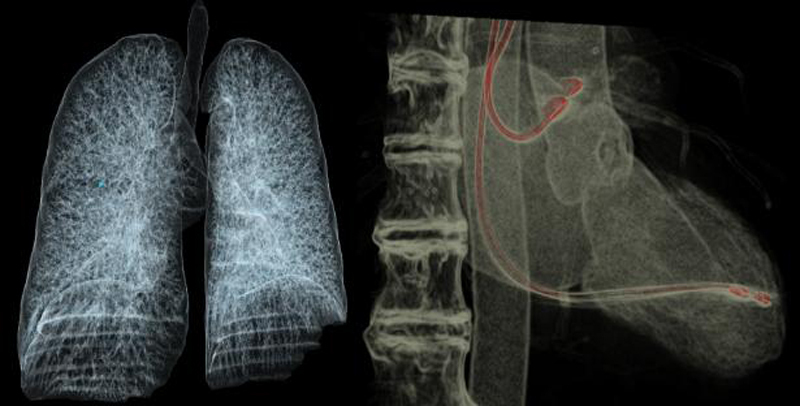

微剂量CTA成像

采用业内最先进液态金属轴承技术的超大热容量球管,结合独有的低千伏、低毫安成像模式,天河640可实现肺部、冠脉等全身各部位大扫描通量、微辐射剂量的体检筛查。低千伏扫描模式有效降低辐射剂量、对比剂总量、对比剂浓度、对比剂注射速率,降低肾功能不全受检者增强检查风险、减少对比剂外渗风险、并可大幅度提升增强检查碘对比剂对比度,提升强化效果;同时,系统还可根据不同患者体型和扫描协议自动推荐扫描管电压,在降低患者扫描剂量的同时,优化对比度噪声比。